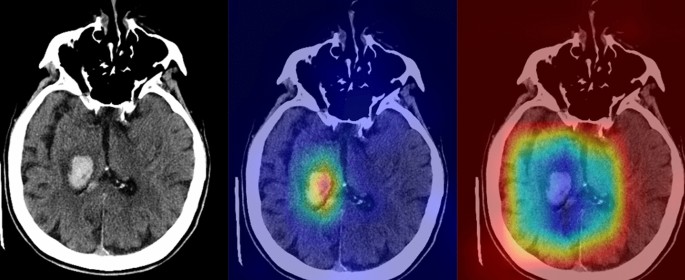

On the four-points scale, the average scan-based scores of the saliency maps generated by the NormGrad method were 3.3 ± 0.6 and 3.1 ± 0.4, whereas the Grad-CAM images yielded average scores of 2.1 ± 0.7 and 1.8 ± 0.5, for the observers. For both observers, the Mann–Whitney-U test showed that the NormGrad provided higher-quality decision maps than the Grad-Cam Method (P < 0.0001). Figures 3 and 4 show representative cases for the predictions of the model. Figure 5 shows several examples of incorrect predictions of the model.

A 68-year-old female with known hypertension (The images were created by the authors using open-source software, Matplotlib v3.5, Python v3). A right thalamic hematoma extended into the adjacent ventricular system on a non-contrast head CT scan (right). NormGrad (middle) method generates more delicate saliency maps than Grad-CAM (left), highlighting the thalamic hematoma and its ventricular extension. The average quality scores were 3.6 points and 2 points for the NormGrad and Grad-CAM, respectively. Please note that the observers evaluated saliency maps with the same color spectrum, and the current color maps are adjusted for representative purposes.